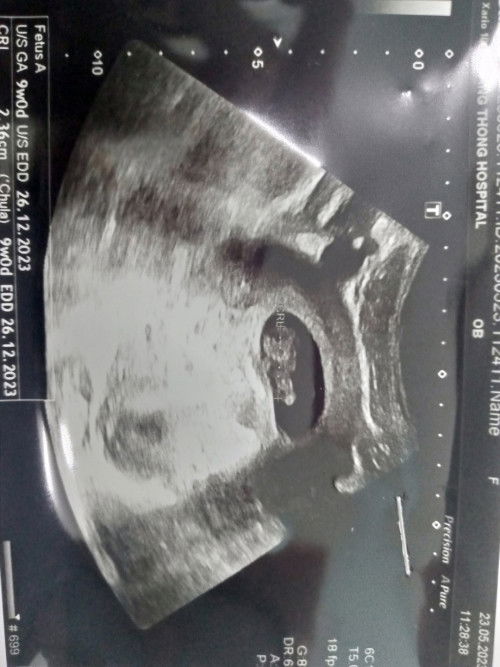

พอดีท้องได้9+4w แล้วมีอาการปวดท้องจี๊ดๆเหมือนโดนเข็มทิ่ม แบบนี้ปกติมั้ยคะ เมื่อวานพึ่งไปซาวด์มา เห็นน้องเป็นครั้งแรก แล้วได้ฟังเสียงหัวใจเค้า เต้นเบาๆ ยังไม่ยินเสียงไม่ชัด เลย แบบนี้เป็นอะไรมั้ยคะ กังวลสุดๆเลยค่ะ ตอนนี้#ขอบคุณล่วงหน้านะคะ #ท้องแรกคะ #ขอคำแนะนำหน่อยค่ะ #ขอบคุณสำหรับคำตอบค่ะ #คุณแม่ๆช่วยแนะนำหน่อยค่ะ